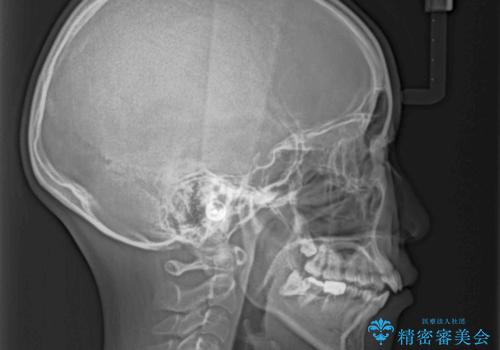

- 口元の突出感を気にして来院された患者様です。

上下左右の第一小臼歯4本を抜歯して口元を下げる治療計画としました。